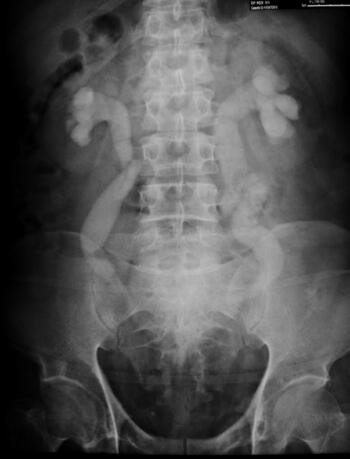

IVU(静脉尿路造影):双肾、输尿管中上段积水、扩张,近髂动脉处以下至膀胱入口长约5cm输尿管段明显变窄(图46-4)。

图46-4 IVU:双肾及输尿管上、中段积水